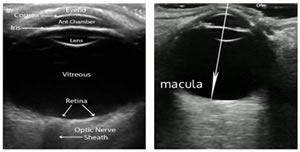

INTRODUCTION The retina, as we know, is a layer of organized neurons which line the posterior portion of the posterior chamber of the eye. The retina consisting of photoreceptors, neurons and support cells, is lined anteriorly by the vitreous and posteriorly by the choroid, and has a central portion called the macula. The macula has a high concentration of photoreceptors and is responsible for capturing central vision. More precisely there is a 1.5 mm central portion in it with the highest concentration of photoreceptors called the fovea, which forms the basis of classification of Mac- On and Mac- Off retinal detachment. Normal anatomical landmarks of the eye as visualized on ultrasonographic imaging are depicted in Figure 1. Figure 1: Normal anatomical landmarks of the eye on ultrasonographic imaging RD (Retinal Detachment) occurs when this layer separates from the underlying epithelium, resulting in ischemia and leading to progressive photoreceptor degeneration which might result in complete blindness of the affected eye if not properly treated or even with delayed treatment and surgeries performed beyond the stipulated time period1, 2 Depending on the type of retinal detachment, the time interval of the surgical treatment is the key to preservation of vision.3 Retinal detachments as described are of three types4: Rhegmatogenous RD (RRD), Tractional RD (TRD) and Exudative and Serous RD. RRD is the most common, and is caused by a tear in the retina (‘Rhegma’ meaning ‘tear’) with consequent extension of vitreous into the potential space below the retina and separation of retina from choroid, requiring surgery. TRD is caused due to pre-retinal membrane formation and scarring which pulls away the retina from its attachment. It is seen in diabetes, trauma, Eales disease and sickle cell retinopathy also indicating surgery. Exudative and Serous RD is less common and along with TRD will not be referred in this study. Rhegmatogenous Retinal Detachment (RRD) can be of two types: Mac- Off and Mac- On RRD. Mac- Off (Macular- Off) rhegmatogenous retinal detachments occur when the retinal detachment also involves the macula and extends to the fovea. Mac- On (Macular- On) retinal detachments on the other hand spare the macula and do not extend to the fovea.4 (Figure 2) a b Figure 2: Ultra-sonographic images of a) Mac- On and b) Mac- Off Retinal Detachments Ultrasound has been evolving in the background of vast advancements in MRI and CT scans in the field of Radiodiagnosis and has proved to be an effective, safe and cost effective radiological investigation giving enormous information in minimum time. However radiologists mostly tend to limit themselves to abdominal or fet al. ultrasound leaving small part ultrasounds mostly to the experts. An area not so commonly explored is ultrasounds or B scans of the eye. It has been found that visualization of the eye is equally possible with a routine ultrasound machine even without the availability of a B scan. Orbital ultrasounds are regularly referred to the Department of Radiology for various pathologies including screening to rule out retinal detachment, particularly prior to cataract surgeries or following trauma or infections of the eye. Radiologists predominantly suffice themselves by reporting the absence or presence of retinal detachment. No classification of the type of retinal detachment is investigated beyond this finding, in majority of the cases. Mac- Off and Mac- On, as described above are classifications of retinal detachment which are less known and very rarely reported by the radiologists, and yet are findings which hold urgent importance in the final outcome of the patients’ vision being restored. Differentiating these two types of retinal detachment give crucial evidence for the outcome of the treatment planned by the ophthalmologist besides giving critical time frame for performing any surgery planned on the affected eye. Overlooking this simple data and a lack of reporting and understanding of the value of this finding may lead to an erroneous miscalculation of the time of surgery and a delay in the surgery, based on this data provided by the radiologist, leading to total permanent blindness. Not only does this radiological finding gives crucial data allowing prompt surgery and saving of the vision, but also provides any unnecessary medico legal repercussions. Retinal detachment on ultrasounds appears as an echogenic linear floating membrane which is attached to the optic disc, differentiating it from PVD (posterior vitreous detachment) where the optic disc is free of the attachment of the membrane.4, 5 (Figure 3) Mac- Off RD can be visualized on ultrasounds as retinal detachment with retina lifted away from the fovea, whereas in Mac- On RD, the retina is attached at the fovea sparing the macula. Mac– Off and Mac– On classification of RD are relatively less known entities and rarely reported or evaluated. Findings of Mac- On RD on urgent sonographic evaluation become critical, requiring urgent surgical repair to prevent total blindness.